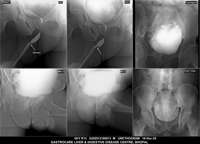

Section: URETHROGRAM Total: 95 images

BaM Enteroclysis Loopogram BaE Fistulogram Urethrogram HSG